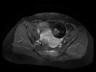

MR images demonstrate left ovarian mass containing fat and soft tissue. Left ovarian mass that contains: Fat (bright in T1 image and fat suppression in T1 fat sat and STIR images), soft tissue-dermoid plug (increased enhancement in T1+C fat sat images).

Conventional radiograph can show calcific and tooth components in the pelvis. An ovarian dermoid is seen as a unilocular cystic adnexal mass with some mural components on ultrasound. CT images demonstrate fat areas with very low Hounsfield values, fat-fluid level, calcification, Rokitansky protuberance. Pelvic MRI shows the presence of fat. Fat suppression technique is used to differentiate between ovarian dermoid cyst and hemorrhagic cyst. Dermoid cyst contains fat and its signal will be suppressed in T1 fat sat and STIR images (2, 3).